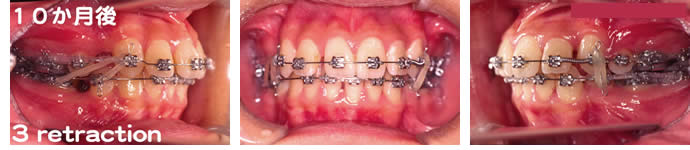

■10か月後

バネとゴムを用いて犬歯を後退させています。